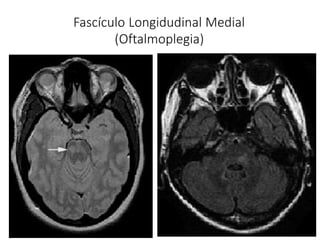

Fascículo Longidudinal Medial

(Oftalmoplegia)